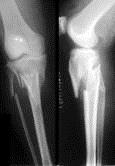

问题 病历摘要: 患者×××,男性,65岁,因车祸致伤左小腿后肿胀、活动受限、疼痛2小时。查体:左小腿上端肿胀,触痛(+),触及在骨擦音,左足伸足母、伸趾功能正常,足背动脉搏动正常。 关于胫腓骨骨折不连或延迟连接的原因,下列叙述哪些是正确的:

选项 A、骨折端血运障碍 B、骨折端感染 C、手法复位粗暴与多次骨折整复 D、骨折端固定不完善 E、骨折软化症,甲状旁腺功能亢进,梅毒,骨质疏松症均可以影响骨折的愈合 F、开放性粉碎性骨折 G、骨折端对位不良 H、骨折端过度牵引 I、肌肉收缩力 J、成骨诱导因子缺乏缺乏